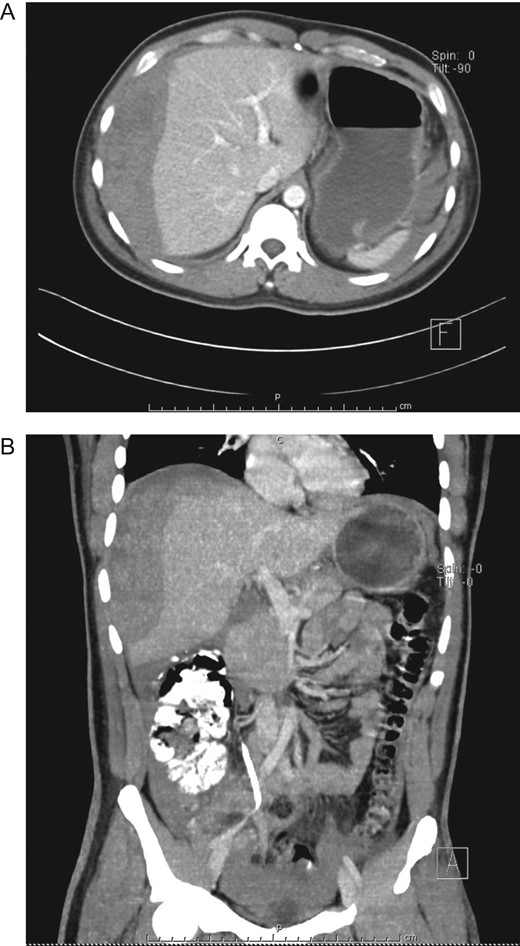

Urologist consultation was required and he underwent ureteroscopic lithotripsy without complications, the ureteral stone was removed and a right double J-stent was placed. Afterward, ESWL was decided for the right nephrolithiasis. A total of 3000 shocks were delivered at a maximum power of 15 kV and a rate of 80 shocks per minute. After the therapy was completed, the patient was discharged without any apparent complication. Nonetheless, 12 h after ESWL, severe pain appeared in his right flank, thus he presented to the emergency room. On clinical examination, a dehydrated, tachycardic and hypotensive patient was encountered. Pain was discovered on his right flank without tenderness. A contrast-enhanced abdominal CT revealed a 9 × 6 × 4 cm3 subcapsular liver hematoma, with an estimated volume of 300 ml that involved almost the entire right liver, without an active contrast material extravasation (Fig. 2A–C).

(A) CT, showing double J-stent and hepatic hematoma. (B) Contrast-enhanced CT, revealing a subcapsular liver hematoma. (C) Contrast-enhanced CT, subcapsular liver hematoma without contrast material extravasation.

After adequate resuscitation and analgesia, his pressure and vital signs were stabilized, laboratory exams did not reveal leukocytosis or anemia however his hemoglobin (Hb) level decreased 4 points from 18 to 14 g/dl. He was admitted for close surveillance and under continuous monitoring. During hospitalization, the patient remained stable without tachycardia or episodes of hypotension, his urinary output was normal and his pain disappeared. However, 48 h after admittance, a new CBC revealed a Hb of 10 g/dl, a new CT was performed and the liver hematoma had grown ~50% (Fig. 3A and B), yet as the patient remained stable, non-operative management of his liver hematoma was decided.

(A) Contrast-enhanced CT, subcapsular liver hematoma 48 h after admittance. (B) Contrast-enhanced CT, the liver hematoma had grown ~50%.